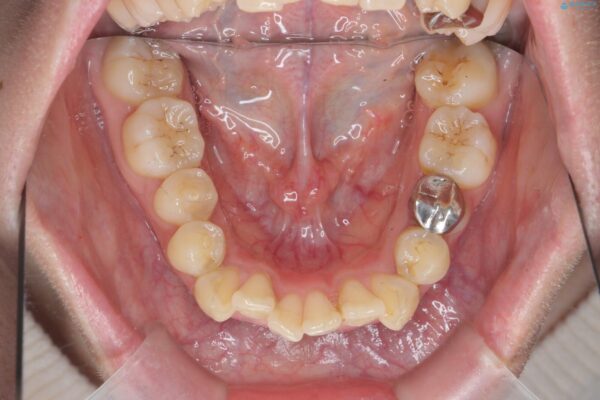

前歯のガタつきの改善を主訴にご来院されました。 特に犬歯の傾きが気になるとのことでした。

犬歯がかなり手前に傾いていましたが、ガタつきはそれほど強くないため非抜歯でマウスピース矯正が可能と判断しました。

治療前

気になる犬歯のガタつきをマウスピース矯正で改善 治療前画像 気になる犬歯のガタつきをマウスピース矯正で改善 治療前画像 気になる犬歯のガタつきをマウスピース矯正で改善 治療前画像 気になる犬歯のガタつきをマウスピース矯正で改善 治療前画像